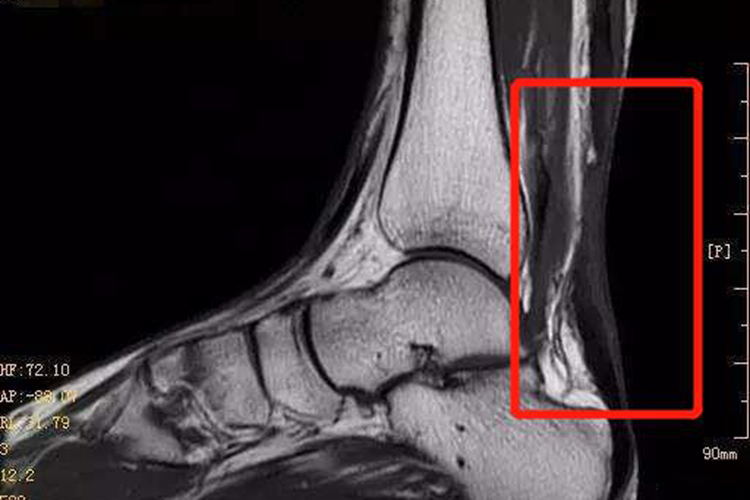

跟腱断裂位于足踝后部,外伤后立即出现足跟部疼痛,局部肿胀、瘀斑,并且会有行走困难、提跟无力、跛行等症状。可在跟腱断裂处扪及压痛及凹陷、空虚感,影像学检查可显示跟腱缺乏连续性。